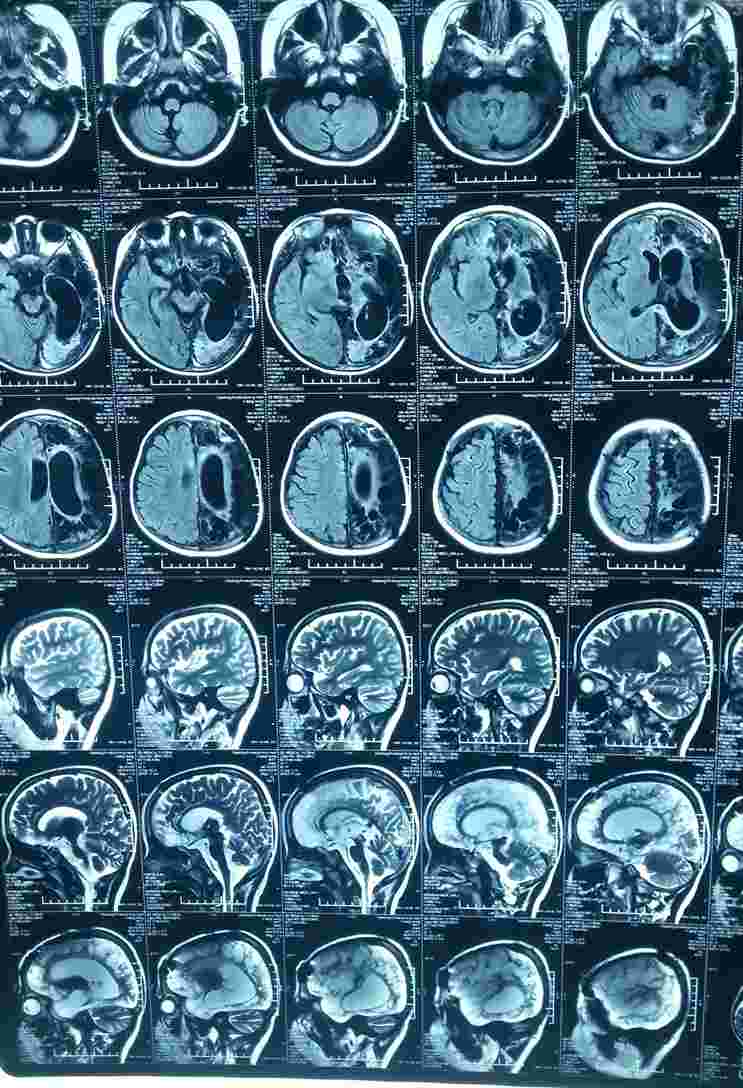

马年农历大年初三,一场厄运降临到临沂6岁男孩李相成身上。那天,患儿屋顶上玩耍时不小心从房顶上跌落,脑部着地,当场颅骨破裂昏迷,急送至平邑县人民医院。 CT显示左侧大脑半球大面积挫裂伤,广泛颅内出血,左头盖骨碎裂,当天行开颅手术将碎骨取出。晚上孩子的瞳孔开始扩散。在重症监护室昏迷32天无任何好转,医生告诉孩子父母:孩子没救了,让他们做好心理准备,就算活过来也可能是植物人。孩子爸爸带着最后一丝希望来到了山东省立医院康复医学科。

患儿2014年3月20日入住山东省立医院康复医学科后,查体发现,患儿意识模糊,表情淡漠,不会说话,对疼痛刺激反应迟钝,右侧肢体肌力0级,无任何情感表达,双眼对光反应迟钝,瞳孔散大。分析患儿病情较重,根据其病情制定了个体化康复治疗计划,包括针灸、语言训练、偏瘫肢体康复训练、平衡功能训练等。每日康复治疗从早晨8点开始至下午5点结束,即使中午午休时间,患儿父母也自行康复。